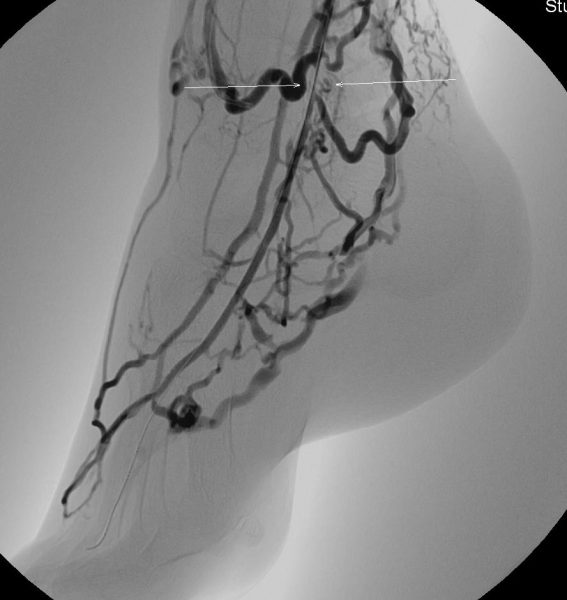

Εικόνα 2. Δημιουργία φίστουλας μεταξύ αρτηρίας και φλεβών του κάτω άκρου: Τα αγγεία που εμφανίζονται να σκιαγραφούνται είναι φλέβες που έχουν ενωθεί με μια αρτηρία και μεταφέρουν αυτές το οξυγόνο στην περιοχή της γάγγραινας.